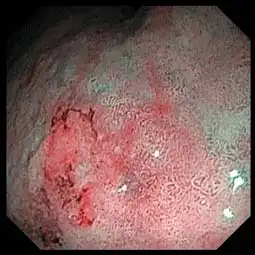

Advanced Image Clarity

Two light guides provide amplifi ed brightness to support accurate depiction of mucosal structures.

White Light NBI